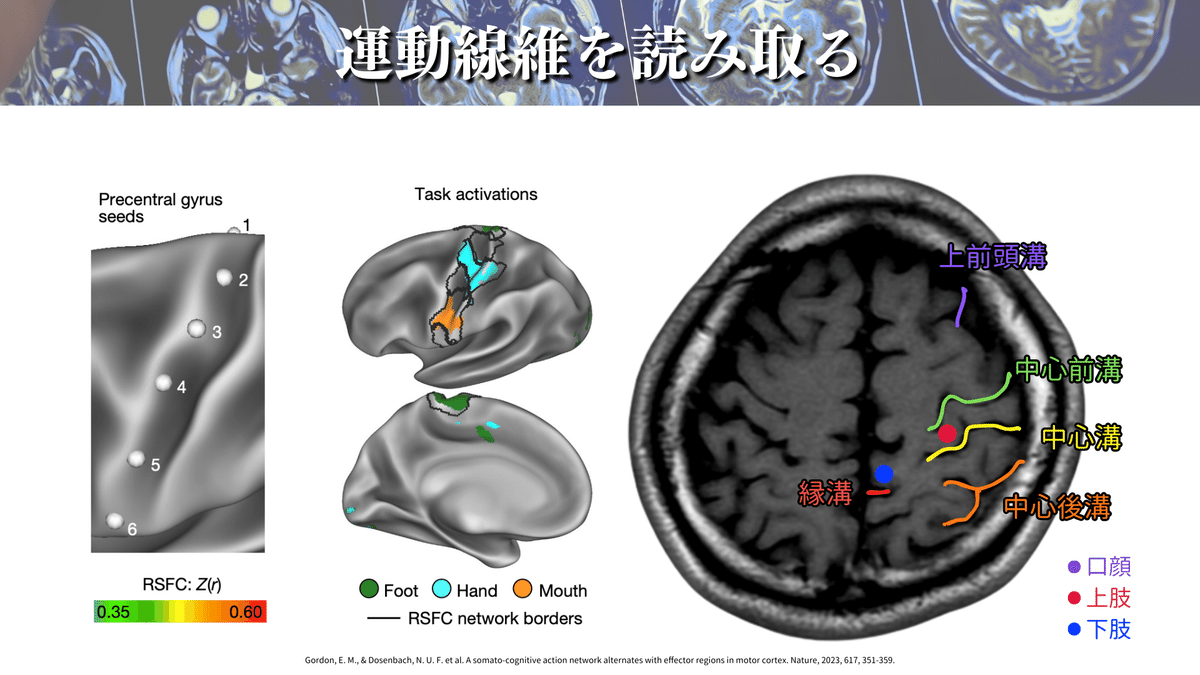

M1にはホムンクルスと呼ばれる身体機能局在があります(下図)!

簡単にいうと手を動かすことに特化した領域や、足を動かすことに特化した領域があるということです🖐️🦶(ちなみにこれを効果器特異的領域と言います)

上図からM1を探すことはできますか?🕵️♀️

M1を探すなら、まずは「中心溝」を探しましょう!

なぜなら、M1は中心前回に位置しており、中心前回は中心溝の前にある脳回だからその名前がついています👍

⬇️のポイントを押えることで、ほとんどの場合に対応できるかと思います☝️

特に僕のおすすめは「pM bracket sing」「handkob sing」「Bified post CG sing」の3つです!

この3つだけでも結構な確率で見つけられますが、6つ全てを押さえておくとより安心かと思います👍

ここまでで、「中心溝」を見つけられたと思いますので、その前方にある「中心前回(M1)」も見つけられたと思います✨

ここからはもう少し踏み込んで、口顔👄、上肢🖐️、下肢🦶の運動線維を大まかに見つけていきましょう!

⬇️の図を見てください!

この図のように下肢🦶は内側にあり、上肢は真ん中あたりでhandknobの周辺にありますね!

ちょっと待った!!!

口顔がないじゃないか!!!

と気づいた方もいるかと思いますが、このレベルでは口顔👄は見えないことが多いんです💦

これに関しては上図を見るとイメージできるかと思いますが、口顔の効果器特異的領域は左の画像の「5」に相当していて、耳よりに位置しています。

なので、このレベルではまだ見えないことが多いんです!